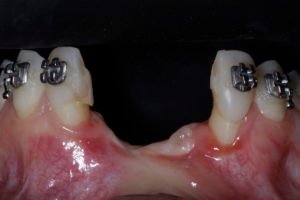

Paciente já havia realizado um procedimento na região anterior da maxila, mas sem sucesso. Em nossa avaliação, a falha pregressa tem relação com a falta de suporte periodontal dos incisivos laterais, que foram extraídos como parte do procedimento agora realizado.

Após a extração dos referido dentes, o retalho de espessura total foi elevado para exposição completa do defeito ósseo. Veja a discrepância dos picos ósseos medial e distal na posição dos laterais, e a anatomia complexa do defeito.